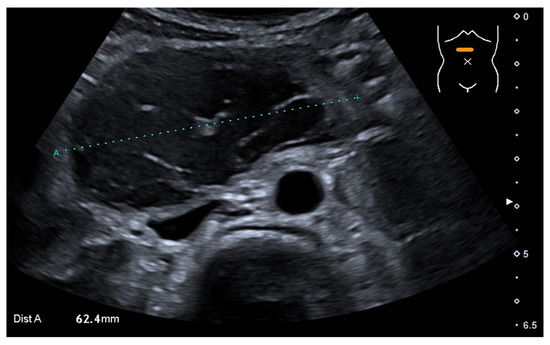

3. Case Report